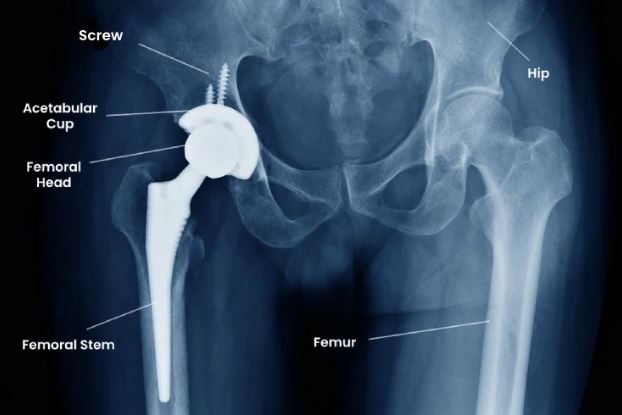

Total hip replacement (THR)

Total Hip Replacement (THR) is a surgical procedure performed to relieve pain and improve mobility in individuals with severe hip joint damage, often caused by arthritis, fractures, or other degenerative conditions. In this procedure, the damaged parts of the hip joint are replaced with artificial components made of metal, ceramic, or high-grade plastic. This helps restore smooth movement of the joint, reduce stiffness, and improve overall quality of life. THR is usually recommended when conservative treatments such as medications, physiotherapy, or lifestyle changes no longer provide relief. After surgery, a structured rehabilitation program, including physiotherapy, plays a crucial role in regaining strength, flexibility, and function of the hip. With proper care and exercise, most patients can return to daily activities, walk comfortably, and enjoy an active lifestyle free from persistent hip pain. s